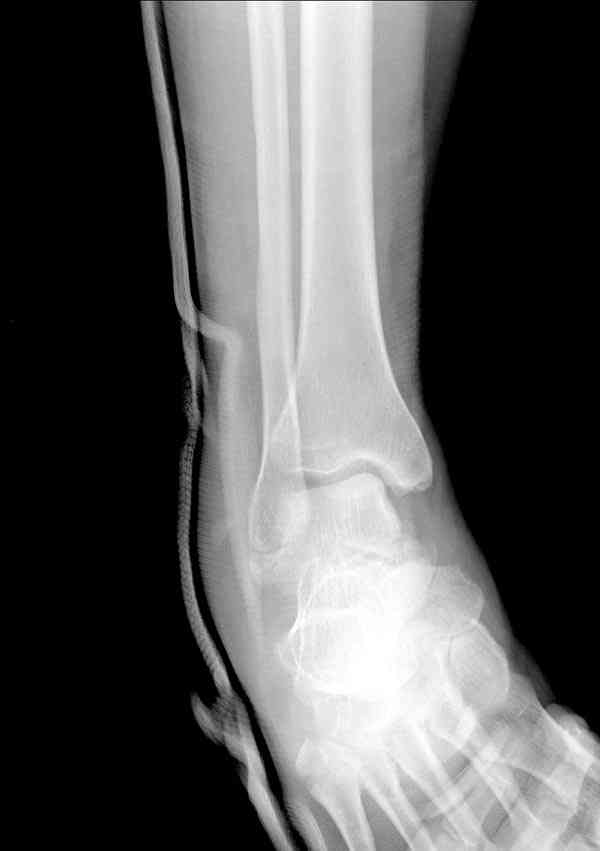

И второй случай из недавней ташкентской практики, (извините за качество ренгенограммы и только в одной проекции) случай падения с высоты (кстати моего друга - известного киноактера) - открытый

смещенный перелом тарана, с переломом переднего края дистального эпиметафиза большеберцовой кости.

При поступлении в приемной сделана первичная обработка с ушиванием открытой латеральной раны и вытяжением за пятку.

Из-за отсутствия времени пришлось оперировать на второе утро, из материала, что имеем на месте, фиксирован двумя шурупами, а третий-это контур сломанного жойстика в 4 мм. На дистальный медиальный конец тибиа antiglide 3.5 мм пластина. Через пару дней выписан и несмотря на предупреждение, самостоятельно начал нагрузку в 4 недели, время не ждет, снимается в боевике в Росийской Федерации.